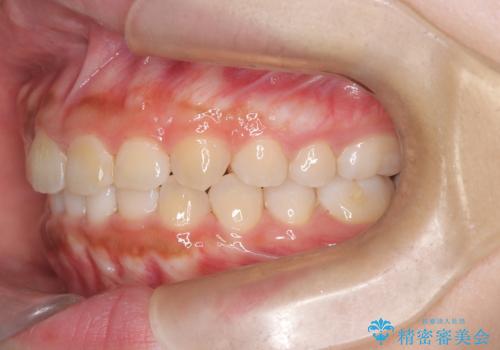

- 歯のデコボコ(叢生)を気にされて来院されました。精密な検査の結果、中等度の叢生と診断。患者様のご希望に合わせ、透明で目立ちにくい**インビザライン(マウスピース矯正)**による治療計画を立案しました。歯を抜かずに、歯列弓(歯が並ぶアーチ)を少しずつ拡大することで、歯が並ぶスペースを確保し、叢生を改善することを目指します。

今回の矯正治療では、透明なマウスピース型の装置インビザラインを使用しました。この装置は目立ちにくく、取り外しが可能なため、食事や歯磨きも普段通りに行えます。治療は、緻密に計算された治療計画に基づき、段階的に作製されたマウスピースを交換していくことで、歯列弓全体を徐々に広げていきました。この歯列弓の拡大により、不足していたスペースを確保し、歯のデコボコを効果的に解消。抜歯することなく、整った美しい歯並びと良好な咬み合わせを獲得していただけました。